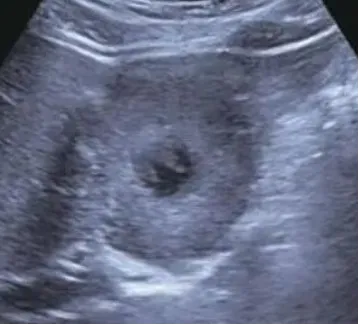

肝脓肿

● 定义:肝脓肿是肝脏的化脓性炎症,可由细菌、真菌或阿米巴原虫等感染引起。病理过程通常包括炎症浸润期、脓肿形成期和脓肿吸收期。

● 超声表现:

1.肝内单个或多个占位性病变。

2.早期呈低回声,边界不清,血流丰富。

3.脓液形成后,呈液性暗区,壁厚薄不均,内壁不平整,内透声差,可见絮状回声,有些可见分层。

4.肝脓肿进一步发展,内透声好,如肝囊肿,但壁厚薄不均。

5.后方结构(后壁)回声增强。